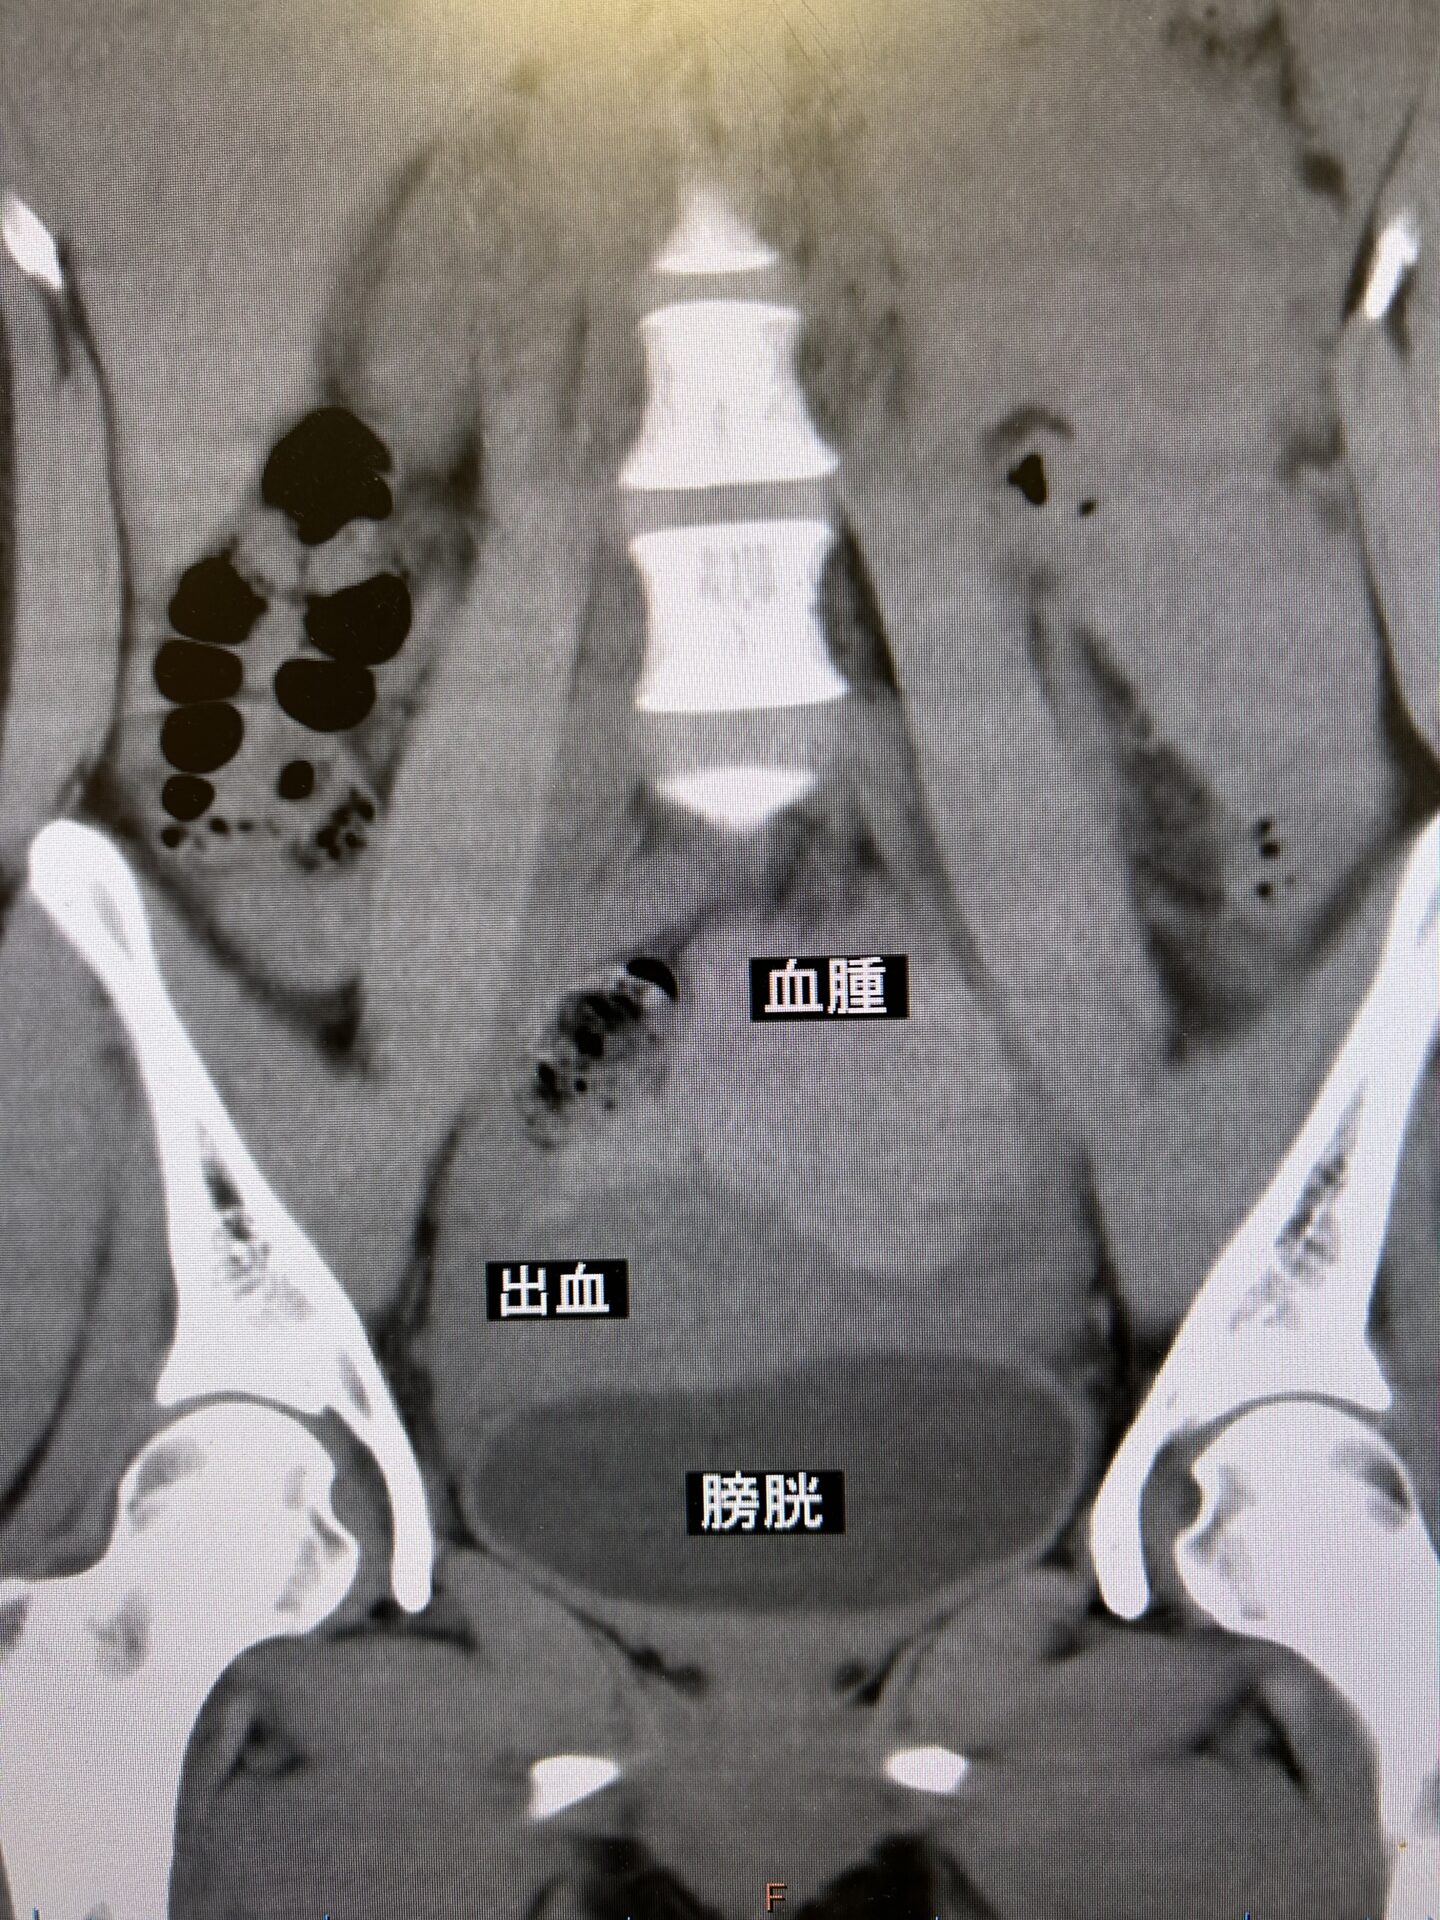

先日40歳台の男性が、前日からズキズキする下腹部痛と排尿時痛を主訴に当院受診されました。夜間も腹痛で眠れなかったとの事。理学的所見上では上腹[read more] -